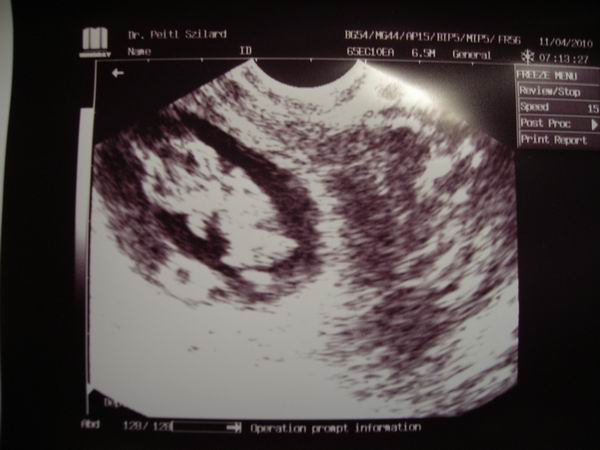

Én mindig csak az u.h-kat várom, de izgulok is miattuk nagyon.Én már olyan rég láttam a babánkat, több, mint 3 hete

Ági, gyönyörűséges a babád